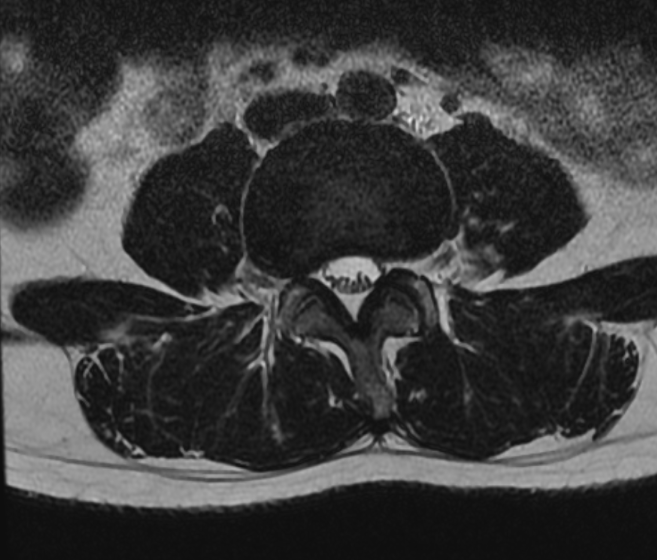

①中央型突出(少见)

男性,31 岁, L5/S1 椎间盘突出,中央型